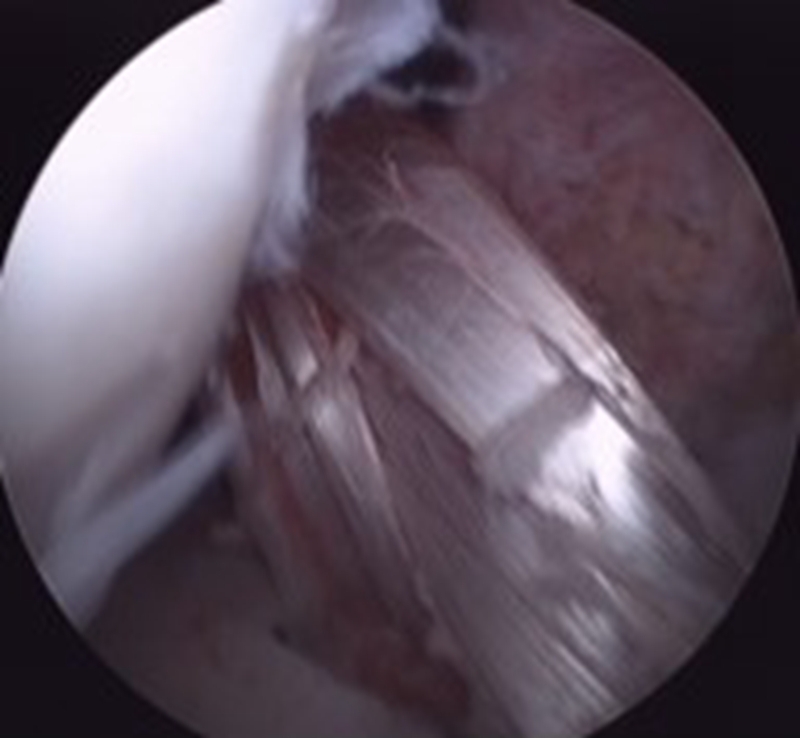

(1)自体股骨-髌腱(中1/3)-胫骨:髌腱中1/3部初始强度为2900N,为正常ACL的168%;并且两端带有骨块,利于固定,为骨性愈合,强度确切。